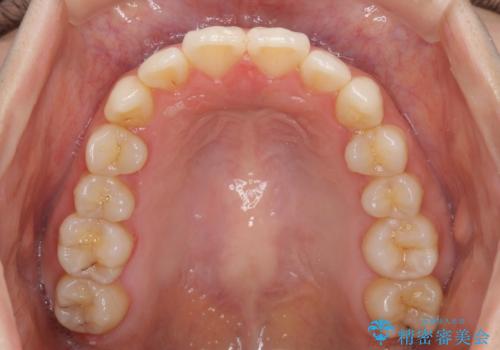

マウスピース矯正は毎日しっかりと装着することがとても大切です。

こちらの方はしっかりと指示を守って装着してくださったため、予定通り治療を終えることができました。